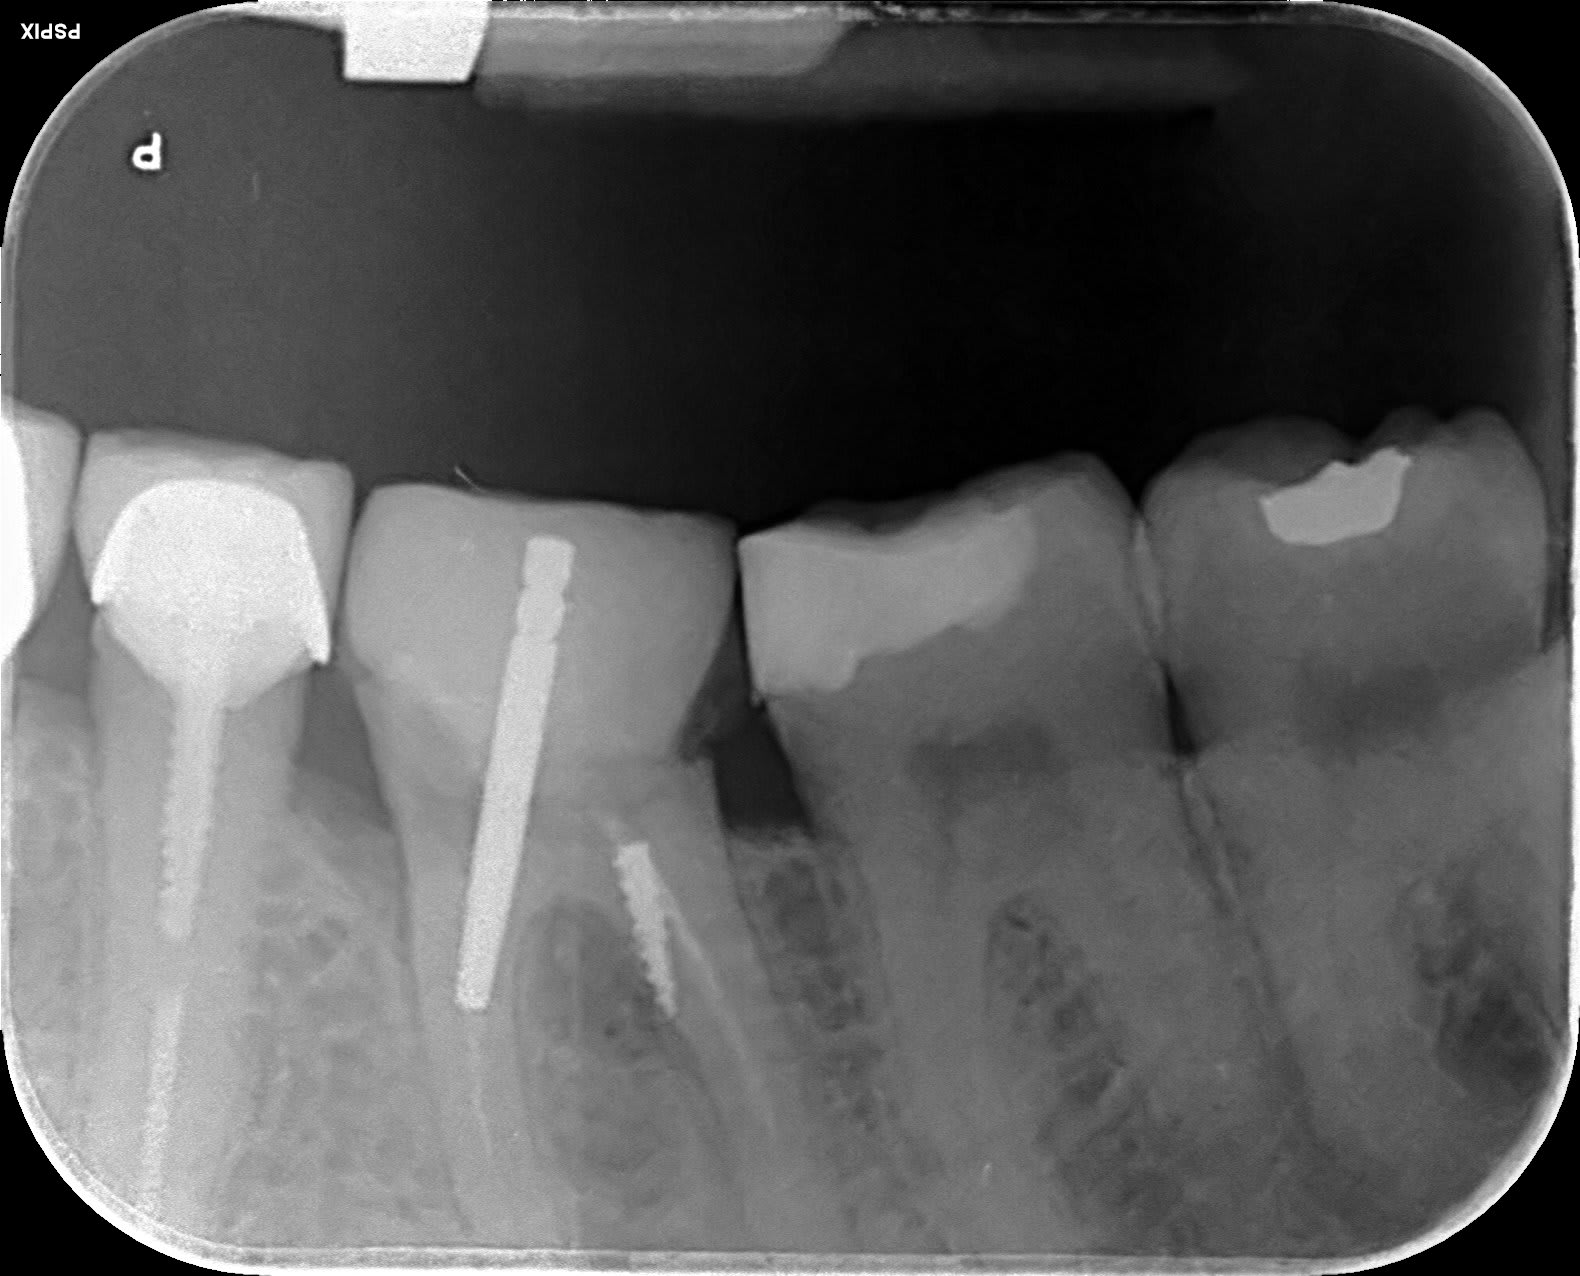

On fait quoi?

On fait quoi lu1sts - Eugenol

Symptomatique?

je te le dis dans 20 min ;-) la patiente arrive.

asympto, je surveille tous les 6 mois. Un jour faudra peut être faire quelque chose.

La prov est scellée au polycarboxylates, donc étanche.

Je me connais, si elle se descellait, je tenterais une CR avec un moignon compo probablement.

L'implant c'est la facilité...

On sent bien la French touch, en plus c'était pas du low-coast!!

Peut être que le confrère qui a mis le tenon, n'était pas le même que celui qui a posé le screw post ?

Bien vu. Le tenon, c'est pas le souci, tu supprimes le surplomb en Ml, ça redresse l'axe et ... et quoi au fait?-)

Le screw c'est chiant, asympto depuis 15 à 20 ans effectivement.

Perso, je surveille l'espace inter radiculaire et j'attends que ça se descelle... qu'il se passe quelque chose.

je pense reconnaître la même philosophie de soins sur la 45, j'espère pas y toucher:-))

Si ya pas de perfo en regard du screw post je m'en coupe une.

Nan pas fait, c'est asympto et ça changerait rien de faire un 3D (voir les recommandations, la prescription d'un 3D doit apporter un bénéfice, là y a pas)... on le saura le jour le l'autopsie:-)

Personne est pour déposer le screw, bourrer au MTA, rte, IC, CR:-))